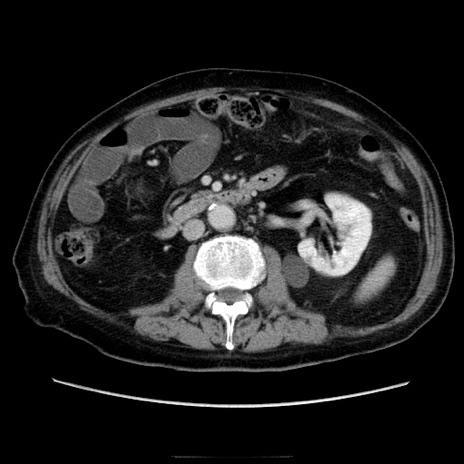

症例21(横断像)

【症例】70歳代男性

【主訴】腹痛

【現病歴】肝硬変・肝細胞癌にてかかりつけの方。約9時間前に食後より腹痛出現。症状が徐々に増悪し、嘔吐出現したため来院。

【既往歴】肝硬変、肝細胞癌(RFA、TACE後)

【身体所見】意識清明、表情苦悶様、BT 36℃、BP 129/78mmHg、P 88bpm、SpO2 97%(RA)、右上腹部から心窩部にかけて圧痛あり、反跳痛なし、筋性防御あり。

【データ】WBC 5800、CRP 0.16